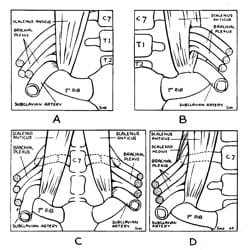

John Sebastian Bach Stopford and E. D. Telford at Manchester University Medical School describe compression of the lower trunk of the brachial plexus by a normal first rib, and report results from 10 patients following resection of the first rib. Stopford and Telford considered the following three key elements as the underlying etiologic factors in development of brachial plexus compression:

- Anatomical relationship of the brachial plexus and the first rib, including anatomic variations of the first rib

- Gradual descent of the shoulder from childhood to adulthood

- Strength and tone of the supporting muscles of the shoulder

In 1939, Eden first demonstrated the role of the clavicle in TOS. Eden operated on three patients with aneurysm or occlusion of the subclavian artery; two with a cervical rib, and one without. At surgery, he demonstrated marked narrowing of the space below the clavicle on arm motion. In patients with a cervical rib or a normal first rib, arterial damage occurred in this narrowed space. Eden stated, “The findings in these three cases suggest that the wall of the subclavian artery is weakened by intermittent compression by the clavicle against a bony obstruction. This is usually provided by…a complete cervical rib, but an abnormal first thoracic rib may do so also.”

1943

Irving S. Wright describes patients with similar symptoms and signs as those with ‘costoclavicular syndrome.’ However, Wright’s patients experience symptoms with hyperabduction of the arms (elevation of the arms above the head). Interestingly, Wright could not reproduce symptoms or pulse obliteration in his patients by using the maneuvers used by Falconer.

Wright went on to test 150 asymptomatic volunteers by performing hyperabduction of their arms while monitoring their pulse. In nearly 90% of volunteers, Wright induced obliteration of the radial pulse, despite the volunteers having no symptoms. In only two of the 150 patients could Wright induce tingling, presumed to represent nerve compression. Interestingly, neither of these patients had a loss of pulse in the same arm position. Wright concluded that clinical obliteration of the pulse was not correlated with compression of the brachial plexus.

Wright also performed anatomic dissections to further understand the underlying mechanism of hyperabduction. He proposed that there were two different mechanisms, which might occur in isolation or in combination in different patients. First, Wright proposed that the space posterior to the pectoralis minor muscle would create “stretching, torsion, and pinching” of the vessels and brachial plexus only in hyperabduction. Second, he proposed that different arm motions, as demonstrated by Eden in 1939 and Falconer in 1943, would cause similar changes between the clavicle and the first rib.